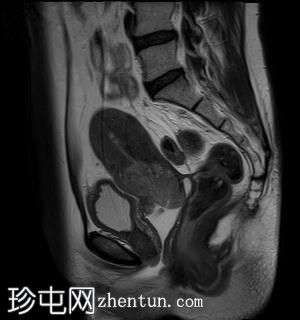

矢状位

T2加权像

可见局部晚期浸润性内生型宫颈癌,肿瘤大小为30 x 32 x 48 mm。该肿瘤已侵犯宫颈前唇和后唇的深层间质,以及子宫肌层的下段。

此外,肿瘤还累及宫旁组织。影像学检查发现异常淋巴结肿大,最大短轴直径(SAD)为10 mm,位于髂总血管分叉处和髂内动脉链下方。该淋巴结肿大在弥散加权成像(DWI)上显示水限制,且增强扫描后可见强化。

宫内节育器(IUD)位于子宫内正常位置。左侧子宫底壁内肌瘤大小为15 x 16 mm(FIGO 4期)。子宫内膜厚度约为3 mm,未见宫腔内病变。双侧卵巢外观正常,未见实性或囊性病变。